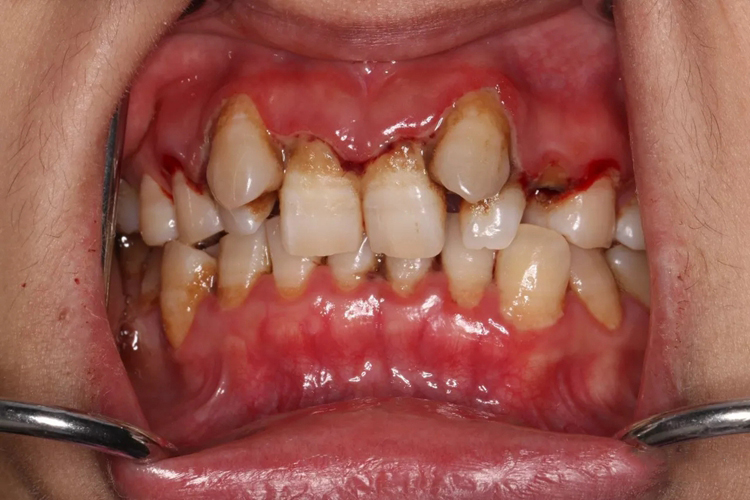

急性坏死性牙龈炎症状为口内有特殊腐败恶臭味,牙龈发红、水肿,龈缘及龈乳头有灰黄色坏死组织,极易出血,前牙牙龈单个或多个乳头坏死时较为严重。

当口腔卫生不良、机体抵抗力下降、组织代谢和血液循环减弱时,细菌在口腔内繁殖,有牙菌斑及炎症形成,可出现急性坏死性牙龈炎。牙龈组织表皮坏死,被纤维素、坏死的白细胞等取代,上皮水肿、变性,毛细血管增生充血,从而出现急性坏死性牙龈炎的一系列症状。